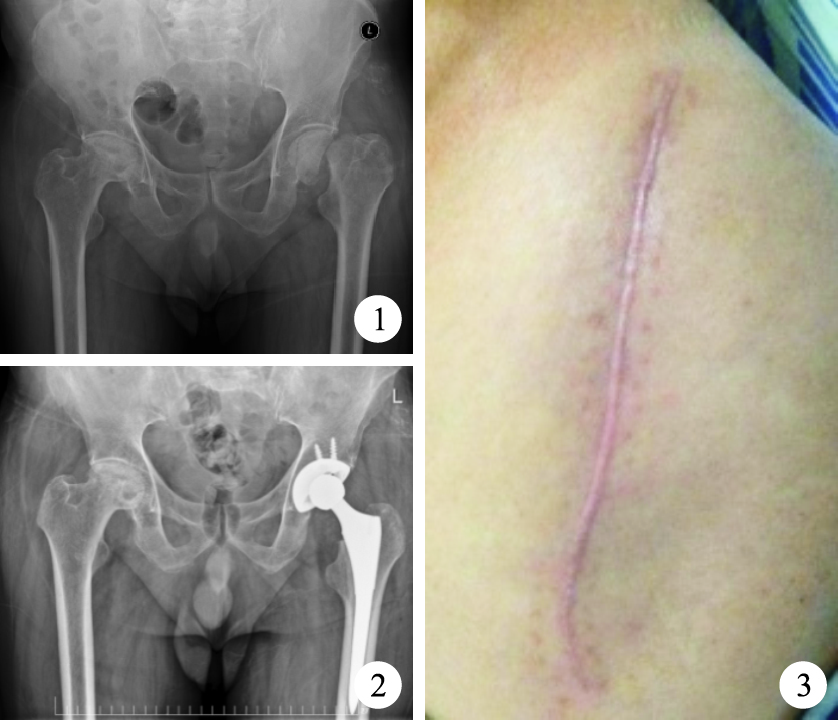

患者 男,65歲。因雙髖疼痛1年余,摔倒致左髖疼痛加重伴活動受限1周于2015年9月入院。3年前因右側內踝皮膚擦傷遷延不愈出現潰瘍,于外院反復清創并封閉式負壓引流治療無好轉,經組織病理學檢查診斷為壞疽性膿皮病,予以醋酸潑尼松治療2個月后潰瘍愈合。入院檢查:左下肢外旋45°,較對側短縮2 cm,左下肢滾動試驗(+),縱向叩擊痛(+),雙髖部“4”字征(+)。X線片示雙側股骨頭缺血性壞死,左股骨頸骨折(圖 1)。于蛛網膜下腔阻滯麻醉聯合持續硬膜外麻醉下,行左髖人工全髖關節置換術。術中見深筋膜及脂肪組織輕度水腫,肌層呈淡紅色,血供稍差;術中失血量100 mL;術畢常規留置引流管。圍手術期除常規預防感染、下肢深靜脈血栓形成及鎮痛等治療外,分別于術前1?h及術后1 h、1 d靜脈滴注氫化可的松50 mg,術后第2 天開始口服醋酸潑尼松,每天3次,每次5 mg,切口愈合并拆線后停藥。術后第2天拔除引流管,指導患者扶助行器下地行走。術后1周內切口均有淡黃色液體滲出,視滲出情況每日1~2次消毒換藥,1周后滲液好轉,2周后切口愈合拆線。患者獲隨訪5個月,X線片復查示假體位置良好(圖 2),左髖部手術切口愈合良好(圖 3),髖關節屈伸活動范圍0~130°,可滿足日常生活需要。